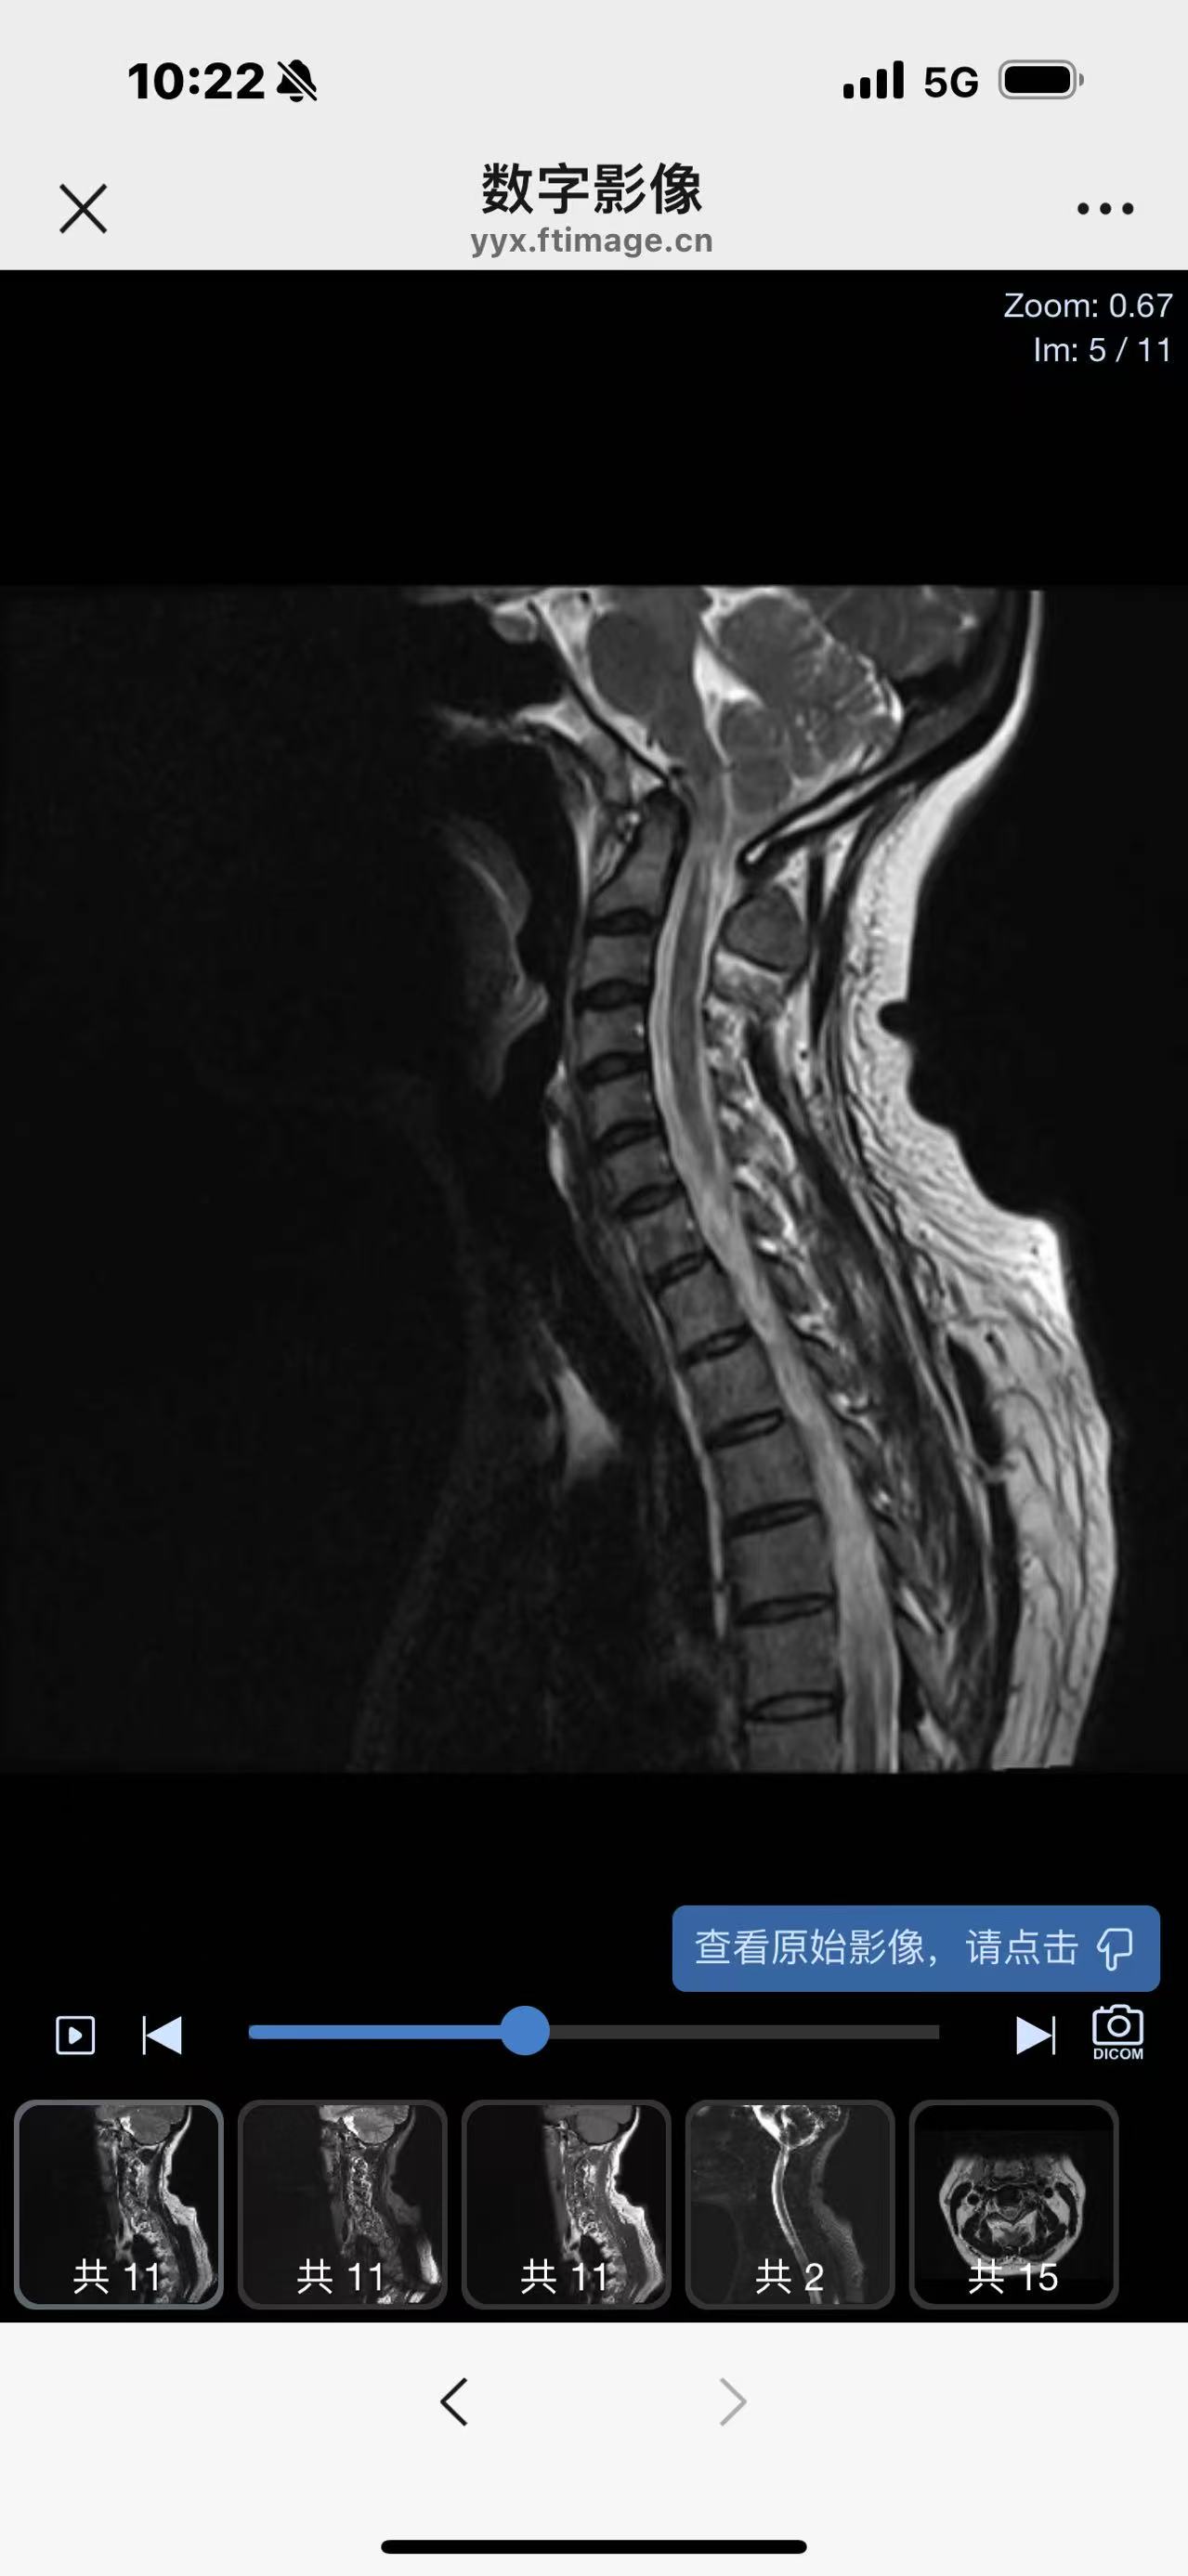

• 诊断:寰枢椎脱位

• 影像:

• 术后影像: